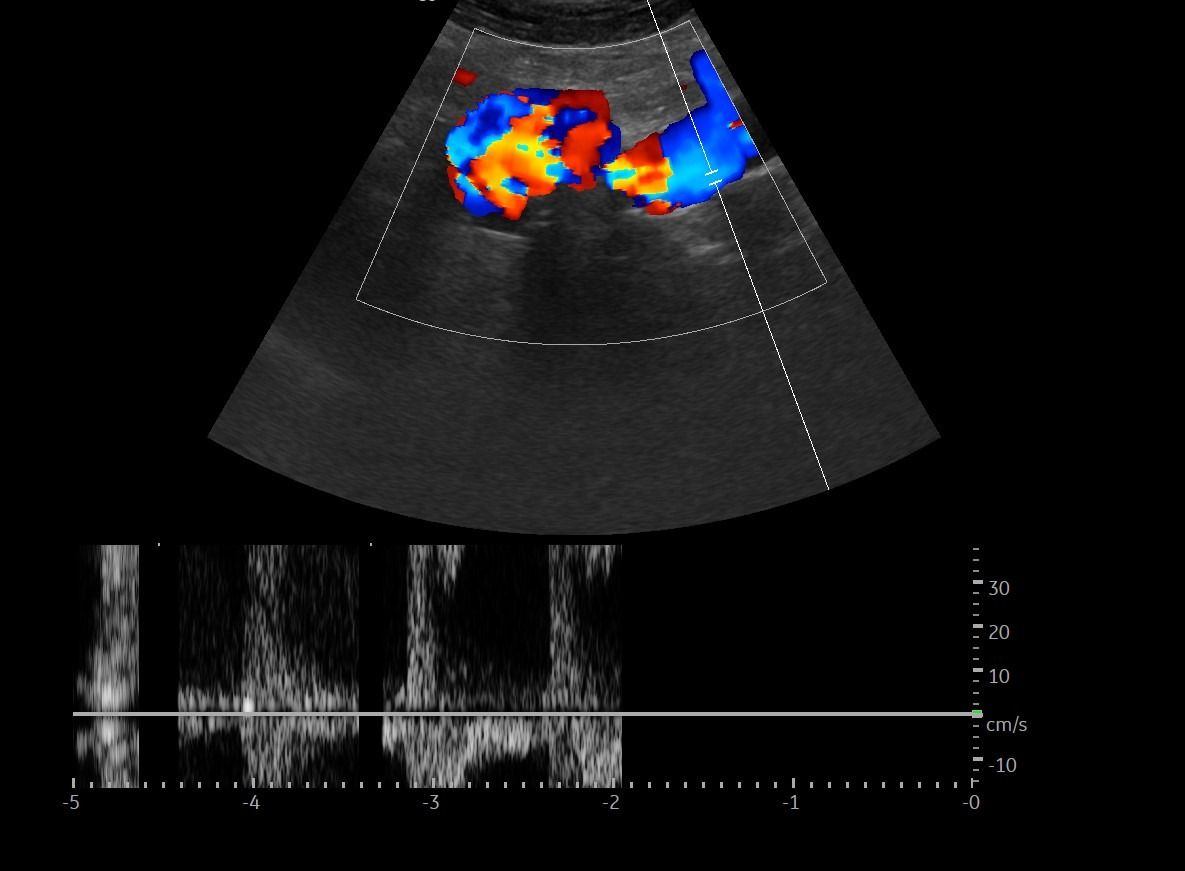

- Αιμοδυναμικές Διαταραχές: Mε τη χρήση του Έγχρωμου και του Παλμικού Doppler μπορούν να μελετηθούν οι ταχύτητες της αιματικής ροής και να ανιχνευθούν πιθανές αιμοδυναμικές διαταραχές.

- Αγγειακή Στένωση: Η αξιολόγηση της αιματικής ροής μπορεί να οδηγήσει στη διάγνωση στένωσης των αγγείων και να υπολογιστεί ο βαθμός της στένωσης.